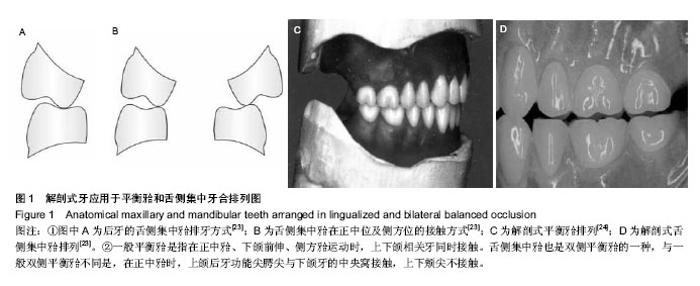

[2] 陈振宇,李江.舌侧集中(牙合)在义齿修复中的研究进展[J].中国老年学杂志,2012,32(14):3122-3123.

[23] Phoenix RD, Engelmeier RL. Lingualized occlusion revisited. J Prosthet Dent. 2010;104(5):342-346.

[24] 徐军.总义齿与可摘局部义齿的设计[M]. 北京:中国大百科全书出版社,2005.